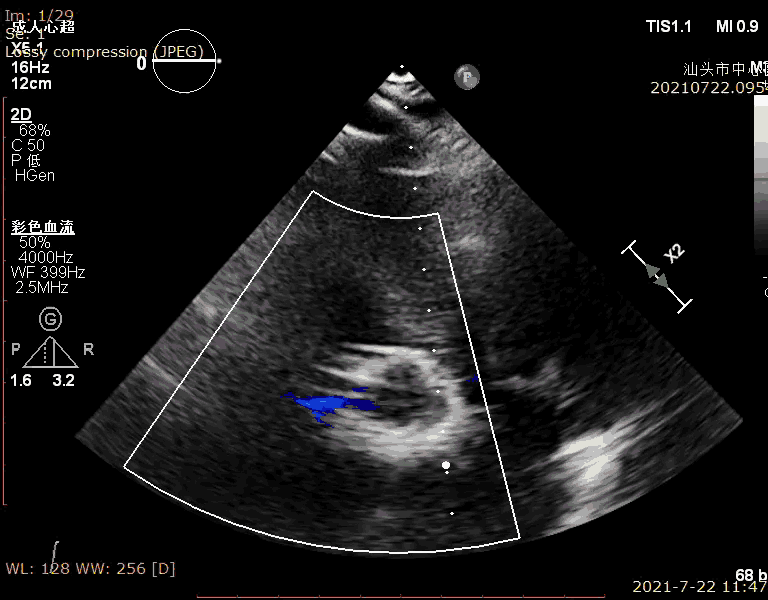

术前超声